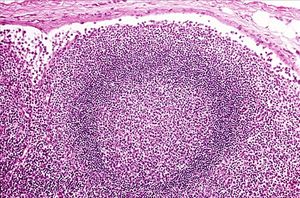

若把癌細胞比喻為出征的軍隊,而我們身體的淋巴結(jié)就像是將被癌細胞攻擊的一座座堡壘,那么前哨淋巴結(jié)將是癌細胞軍隊出征路線上第一座防御關(guān)卡。如果癌細胞軍隊尚未侵犯這第一座堡壘,我們就可以推測接下來的淋巴結(jié)也尚未遭到癌細胞軍隊的攻擊。因此,手術(shù)時取下前哨淋巴結(jié)檢查是否有癌細胞侵犯,可以做為腋下淋巴結(jié)是否已經(jīng)受到癌細胞轉(zhuǎn)移的指標,用於確定癌癥疾病分期,并做為日后后續(xù)化學(xué)治療的參考;并且也可以避免不必要的腋下淋巴廓清手術(shù)。

前哨淋巴結(jié)攝影可幫助外科醫(yī)師精確定位前哨淋巴結(jié)進行切片。若前哨淋巴結(jié)沒有腫瘤侵犯,就不需要再接受大范圍的淋巴廓清術(shù)。這樣一來,對於早期惡性腫瘤的患者而言,手術(shù)時間大幅變短、出血少、傷口小,并可減少因淋巴結(jié)摘除而產(chǎn)生淋巴水腫或其他并發(fā)癥的情形。且前哨淋巴結(jié)病理檢驗結(jié)果可供醫(yī)師進行進一步的治療評估計畫。